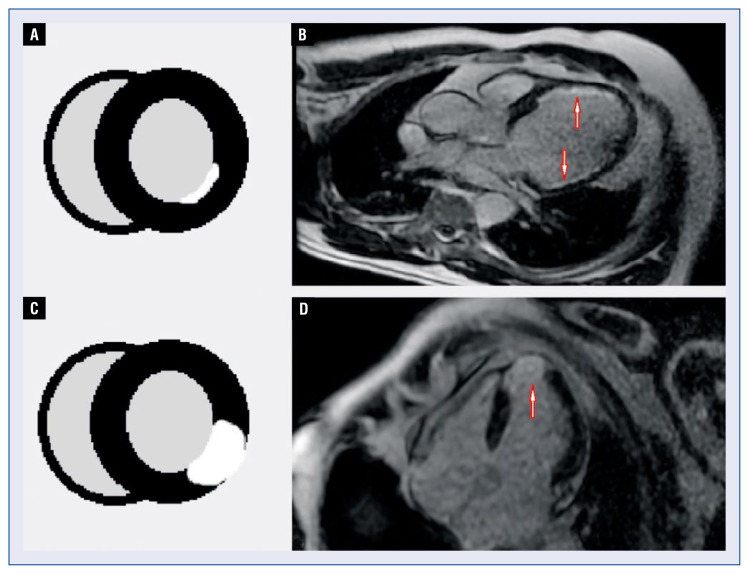

Coronary chronic total occlusions (CTOs) are a common finding on coronary angiograms of patients with coronary artery disease, with an incidence ranging from 15% to 25%. Despite this high incidence, the proper treatment strategy in those patients often remains unclear. There are some observational studies suggesting that successful revascularization of a CTO can reduce angina symptoms, improve quality of life, improve the left ventricular ejection fraction, and lower mortality. However, not all patients will benefit from revascularization. Pre-procedural assessment of left ventricular function, ischemic burden, and viability seems to be crucial for a good outcome of the revascularization. The aim of this review is to compare currently available non-invasive imaging modalities with regard to utility in evaluation of patients with CTOs.